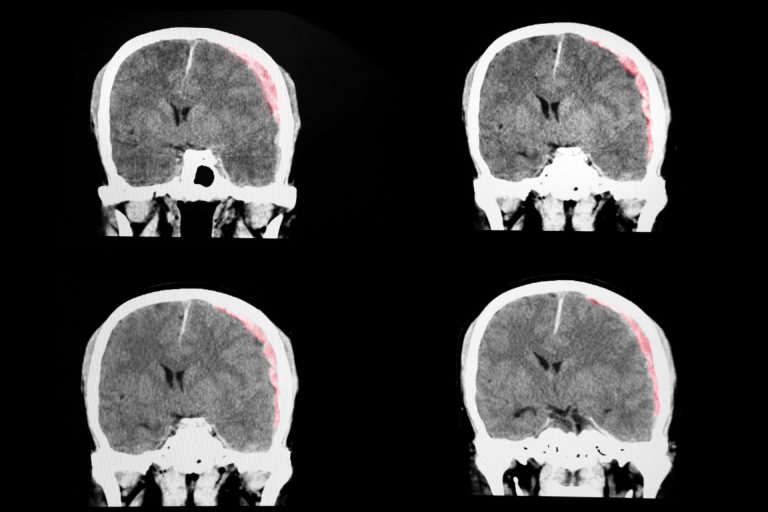

Wie werden vestibuläre Erkrankungen diagnostiziert?

Ärzte nutzen die Informationen aus der persönlichen Krankengeschichte und die Befunde der körperlichen Untersuchung als Grundlage, um diagnostische Tests anzuordnen, womit sie die Funktion des vestibulären Systems untersuchen und alternative Ursachen der Symptome ausschließen.

Wenn die medizinische Behandlung nicht bei der Kontrolle des Schwindels effektiv ist und andere Symptome durch die Störung des vestibulären Systems verursacht werden, kann ein chirurgischer Eingriff in Erwägung gezogen werden. Die Art des Eingriffs hängt bei jedem Einzelnen von der individuellen Diagnose und dem Gesundheitszustand ab. Chirurgische Eingriffe bei peripheren, vestibulären Erkrankungen sind entweder korrigierend oder destruktiv. Das Ziel der korrigierenden Operation ist die Funktion des Innenohrs wiederherzustellen oder zu stabilisieren. Das Ziel der destruktiven Operation ist die Produktion der sensorischen Information oder die Weiterleitung dieser Information, vom Innenohr zum Gehirn, zu stoppen.